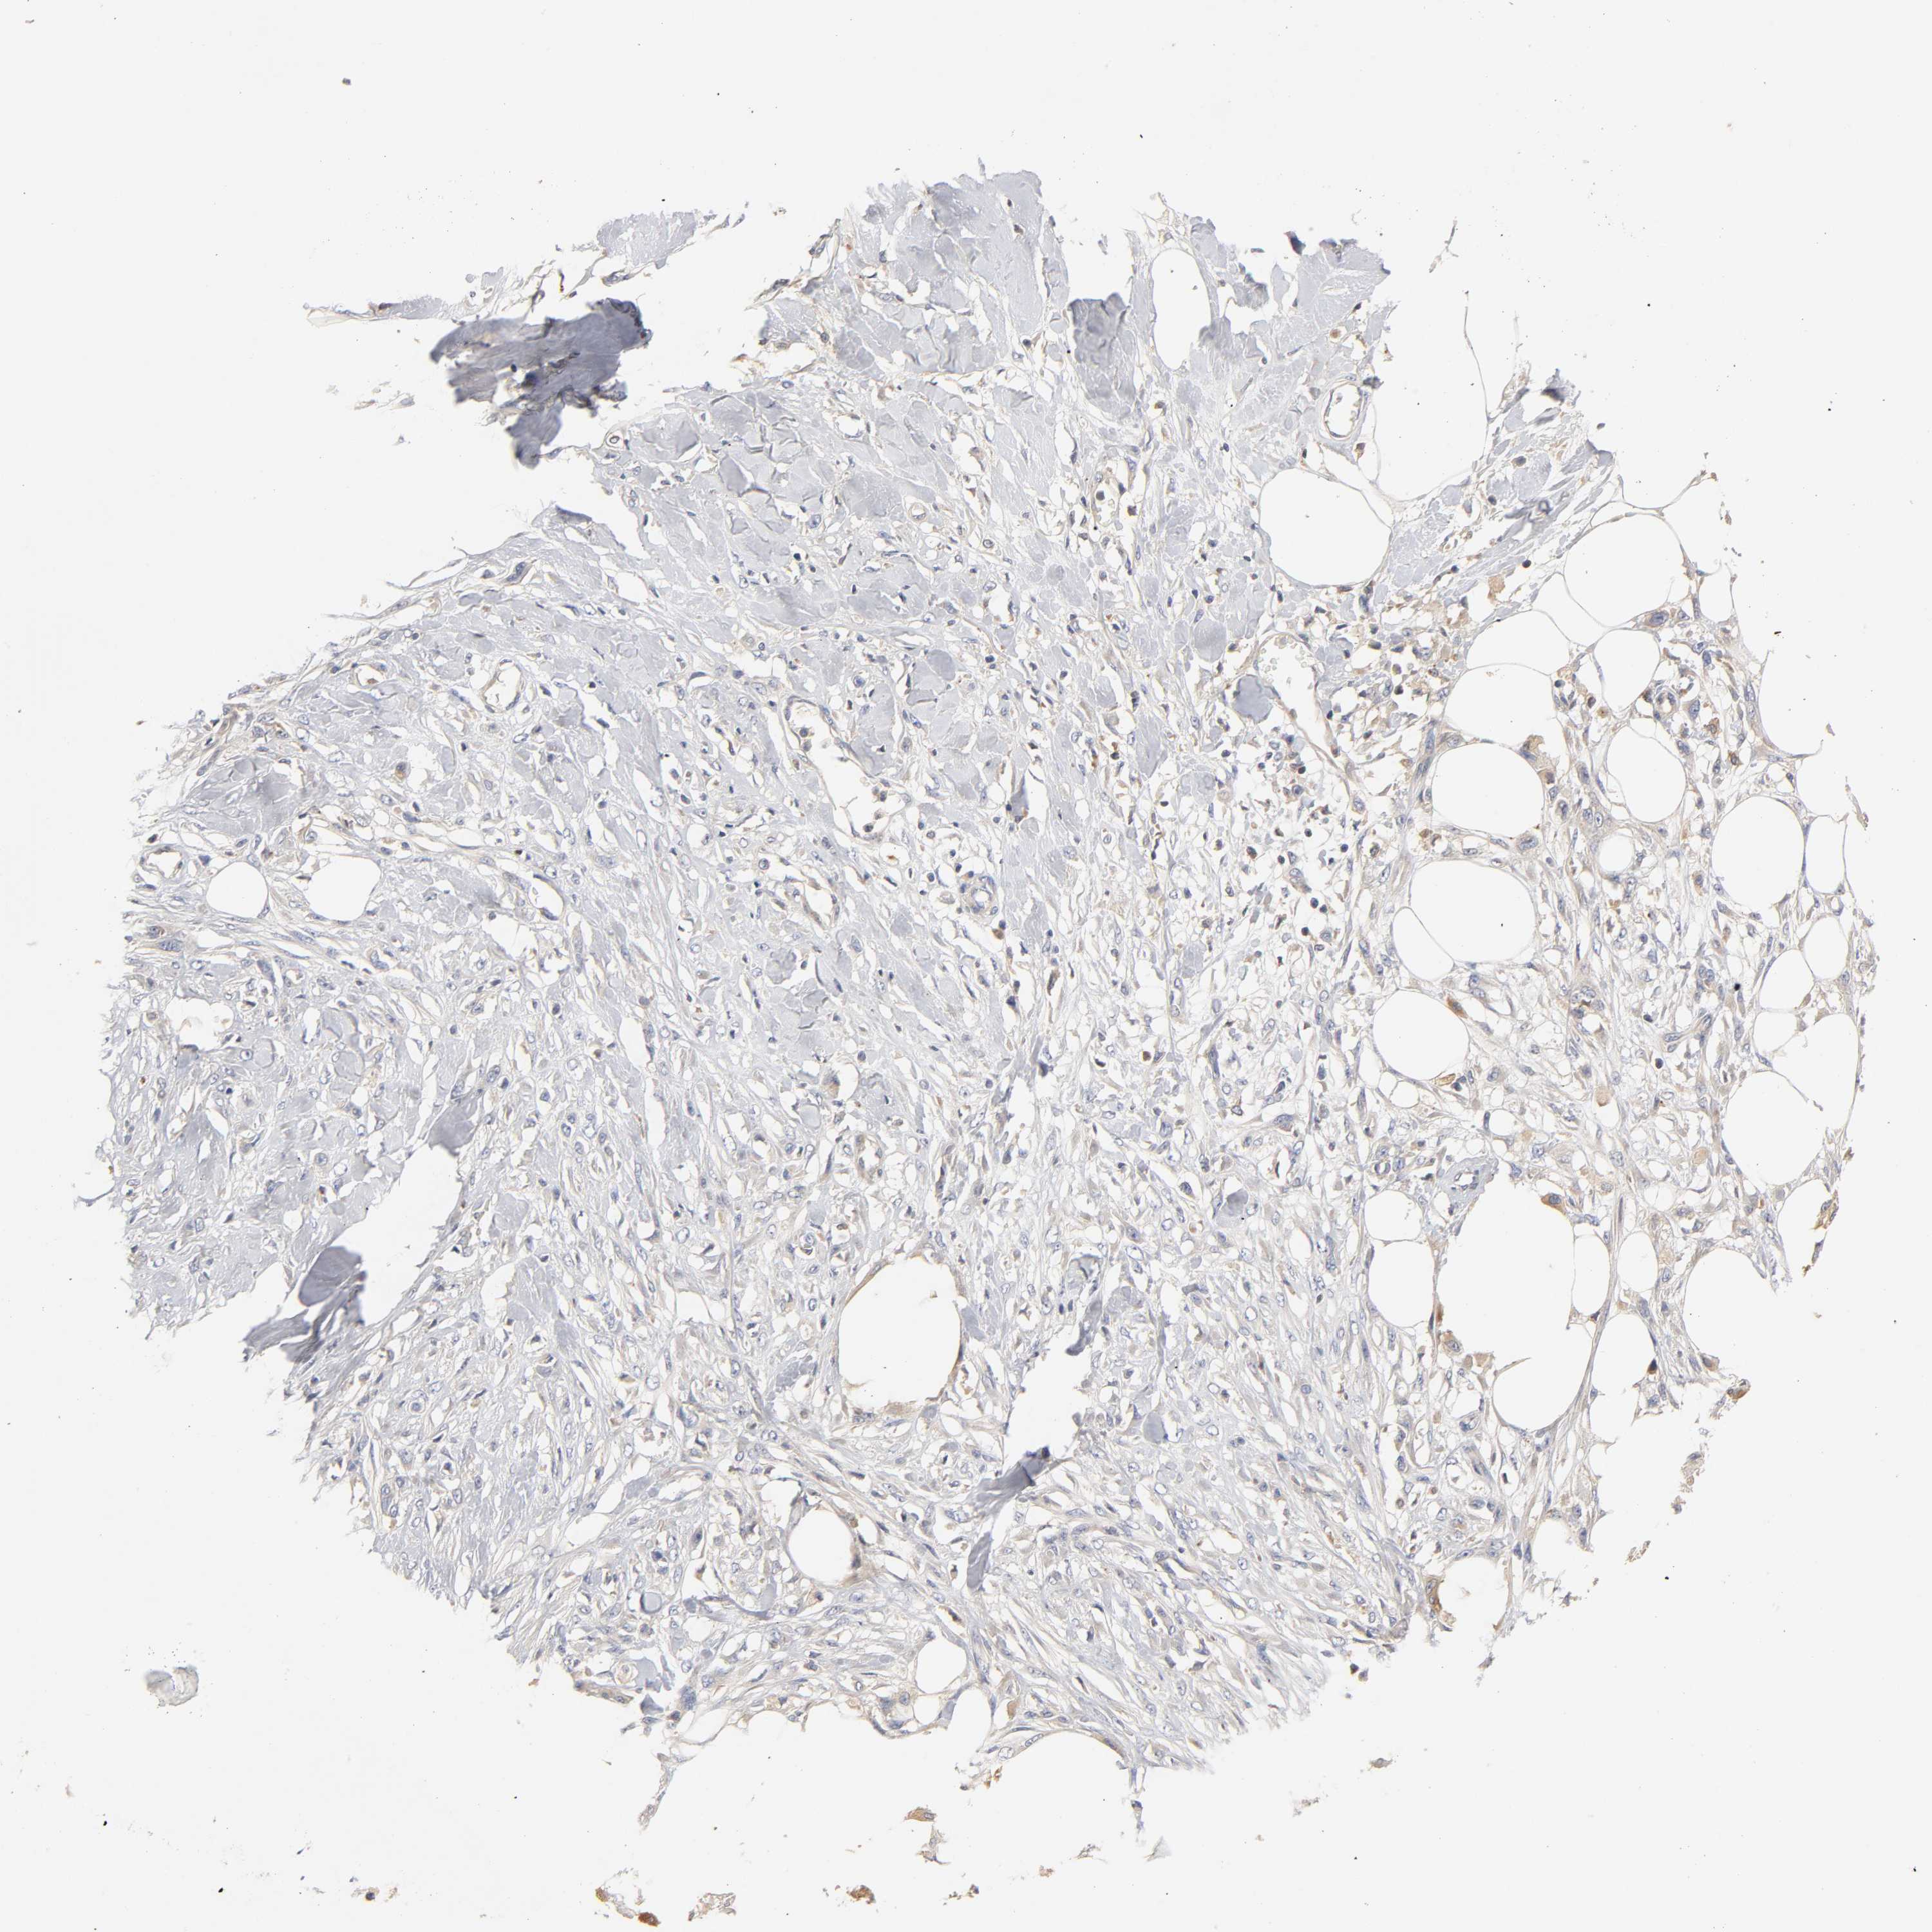

SKIN CANCER - Protein expressioni

A mouse-over function shows sample information and annotation data. Click on an image to view it in a full screen mode. Samples can be filtered based on level of antibody staining by selecting one or several of the following categories: high, medium, low and not detected. The assay and annotation is described here.

Antibody stainingi

Antibody staining in the annotated cell types in the current human tissue is reported as not detected, low, medium, or high, based on conventional immunohistochemistry profiling in selected tissues. This score is based on the combination of the staining intensity and fraction of stained cells.

Each image is clickable and will lead to virtual microscopy that enables deeper exploration of all samples and also displays staining intensity scores, fraction scores and subcellular localization as well as patient and tissue information for each sample.

Antibody CAB005052

Squamous cell carcinoma, NOS

Basal cell carcinoma